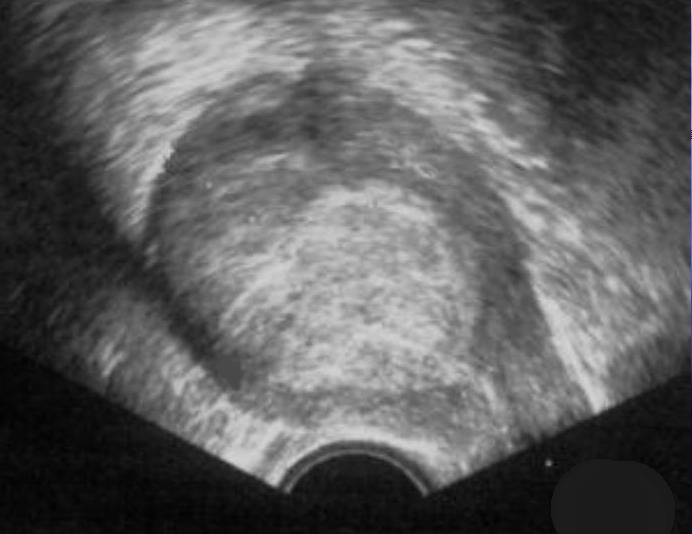

Das Bild zeigt eine vaginale Sonographie eines Endometrium - Ca mit Serosa - Infiltration (Quelle: CA Dr. Müller, Salzwedel)

Sono T3a